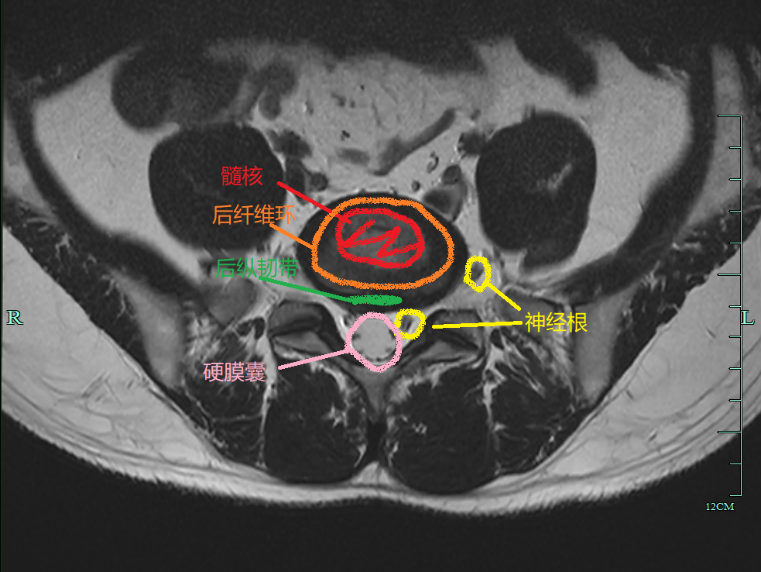

腰椎间盘退变分级常用 pfirrmann 分级,根据腰椎间盘在 T2 序列上信号减低程度及形态变化分为 1 ~ 5 级。

III 级:椎间盘的结构不均匀,呈不均匀的中等信号强度,核与环之间界限不清楚,椎间盘高度正常或轻度塌陷。

IV 级:椎间盘结构不均匀,呈低信号的深灰色信号强度。核和环之间的界限消失,椎间盘高度正常或中度塌陷。

V 级:椎间盘结构不均匀,黑色低信号,髓核与纤维环之间的界限消失,椎间盘重度塌陷。

椎间盘退变 pfirrmann 分级,图示 A ~ E 依次为 I ~ V 级的 T2 矢状位图像,图源:DOI:10.1097/00007632-200109010-00011